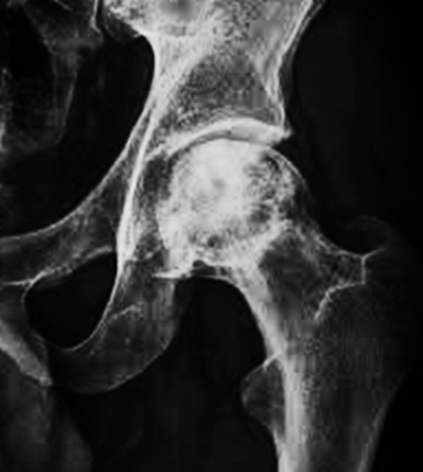

1. A 38-year-old female presented with a chief complaint of chronic pain in the left hip.

2. The pain had progressively worsened following a fall two weeks before presentation. The patient has a history of being a professional athlete.

3. Radiographic imaging of the hip was obtained for further evaluation.

Preoperative Radiographs:

There is bilateral avascular necrosis (osteonecrosis) of the femoral heads. The left femoral head demonstrates flattening with associated subchondral collapse of the articular surface. Superimposed mild secondary osteoarthritis is present bilaterally, characterized by joint space narrowing and a large subchondral cyst in the superior aspect of the left acetabulum. Additionally, an intra-articular osteochondral loose body is noted inferior-medial to the left hip joint. The remainder of the pelvic structures appears intact.